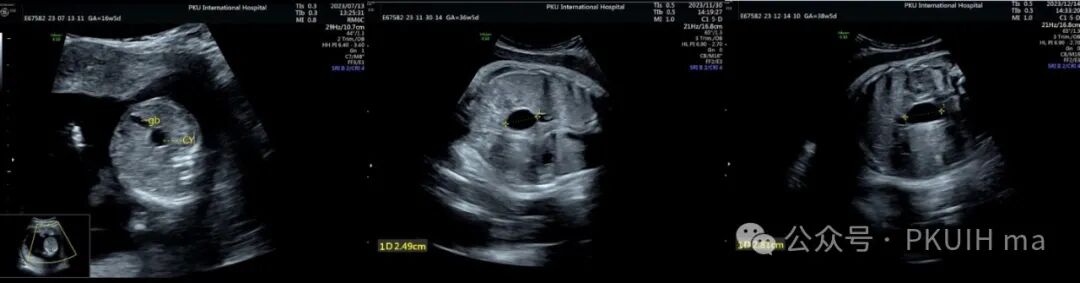

上图是孕16周发现的胎儿胆总管囊肿,在定期的随访观察中胎儿各项状况良好,胆总管囊肿变化不大,最后足月阴道分娩

胆总管囊肿是罕见的先天性胆道囊性扩张,可按受影响的胆道部分分类。最常见的形式包括梭形扩张的常见胆管: 类型 I,占85-90% 的病例。几乎所有产前诊断的病例都属于这种类型(如下图)。其他形式包括常见胆管憩室(II 型)、十二指肠内或胰内胆总管囊肿(III 型) ,以及多发性肝外囊肿伴或不伴肝内囊肿(IV 型)。卡罗利氏病包括单个或多个肝内囊肿伴有肝纤维化和正常的肝外胆管树(V 型)。胆总管囊肿是一种罕见的异常现象,估计发生率为十万分之一至十五万分之一至二百万分之一。这在女性(2.5:1)和亚洲人群中更为常见。